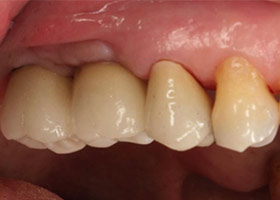

上排缺牙區